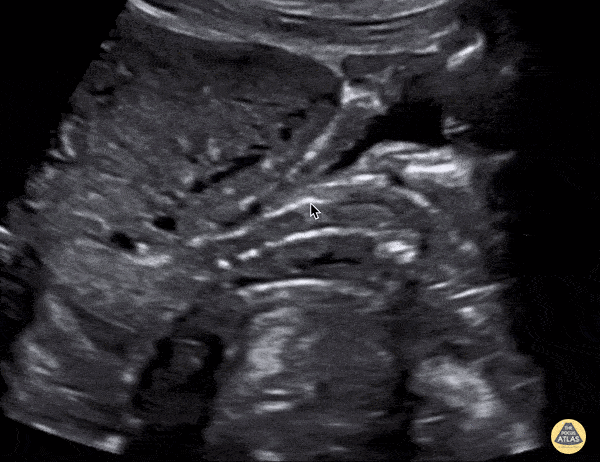

OB/Gyn - IUD in Sagittal Plane

Patient came to the ED due to flank pain. Renal ultrasound was performed by me with the US team. Upon looking for the bladder, I saw my first IUD via US which appeared hyperechoic. ParaGard has been shown to be more than 99% effective. Mehtab Galeh, MD, @GalehMehtab